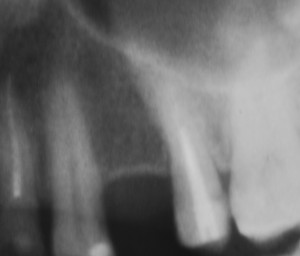

Закрытый синуслифтинг относительно малотравматичен и позволяет поднять дно гайморовой пазухи в пределах 1-4 мм, не прибегая к расширению операционной раны (рис 9, 10, 11):

Рисунки 9, 10, 11. Рентгенограммы области имплантации: слева – до операции, в центре – сразу после операции имплантации в сочетании с закрытым синуслифтингом, справа – через 12 месяцев после протезирования.